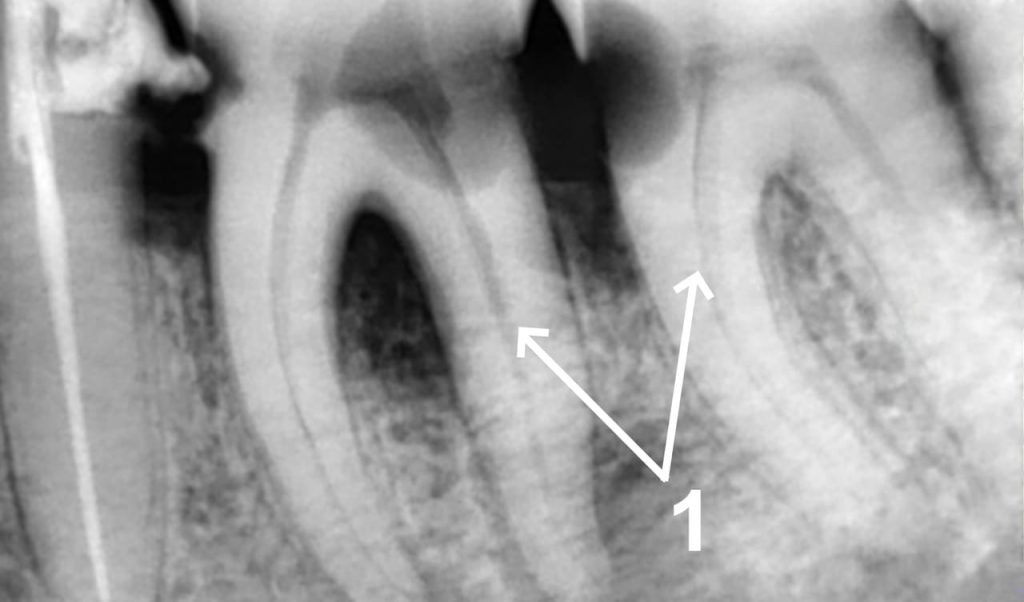

1. A patient complains of increasing nagging pain in the lower jaw teeth (36, 37 teeth), which intensifies after eating cold food or when food gets stuck between the teeth. 1 - A focused X-ray shows a cavity on two teeth. The decay was not treated in time, which resulted in pulp infection in the root canals - an absolute indication for endodontic treatment. Root canal treatment was performed in one visit under local anesthetic.

1. Sealing of the root canals - a guarantee for a positive prognosis. A crown restoration with photopolymer, recommendations on home oral care with a focus on interdental spaces as prevention of such diseases. 2 - Check-up X-ray after root canal filling.